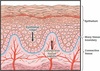

Connective tissue is comprised of a gel-like substance, fibers, and few cells

The gingival connective tissue is comprised of a gel-like substance,

protein fibers, and cells.

The deep extensions of epithelium that reach down into the connective tissue are termed:

C. Epithelial ridges

Epithelial ridges—deep extensions of epithelium that reach down

into the connective tissue. The epithelial ridges are also known as rete pegs.